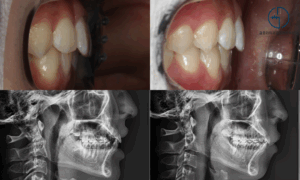

상봉역 교정치과 좁은 악궁(V-shaped arch)으로 인한 심한 총생, 어떻게 해결할까?

사람을 처음 만나는 자리에서 미소를 지으면 호감도가 높아진다는 것은 누구나 아는 사실입니다.😊 하지만 치열이 콤플렉스인 경우, 앞니를 드러내며 환하게 웃는 것 자체가 큰 부담이 될 수 있습니다. 23.11.17 ➡ 특히…